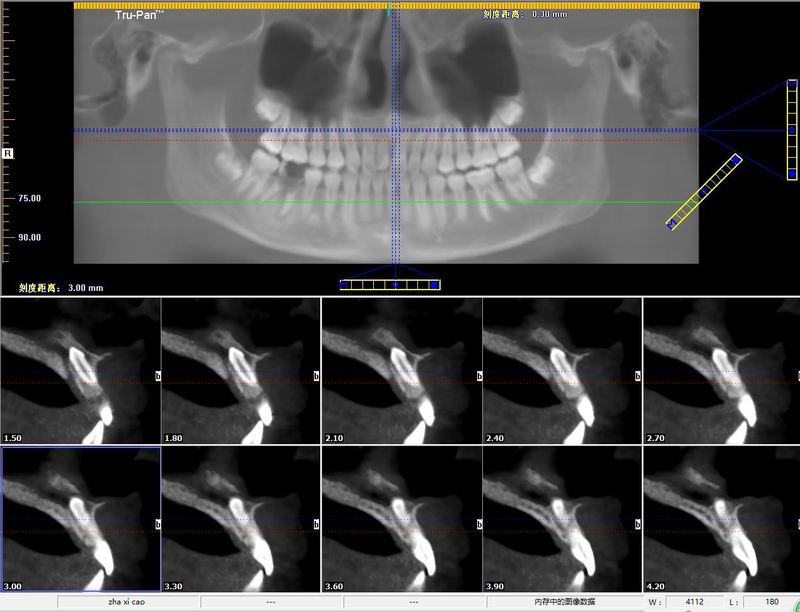

治療前患兒替牙列期,8顆多生埋伏牙,形態(tài)各異,經(jīng)兒童牙病科會(huì)診需要拔除其中6顆(考慮另外兩顆拔除時(shí)可能損傷恒牙胚),同時(shí)要求拔除滯留乳牙。我們術(shù)前通過(guò)CBCT對(duì)每一個(gè)牙進(jìn)行三維重加,并用不同的顏色進(jìn)行標(biāo)注(黑色標(biāo)記為待拔除多生牙)。從而保證了手術(shù)中的精準(zhǔn)合快速。治療后治療后3天患兒替牙列期,8顆多生埋伏牙,形態(tài)各異,經(jīng)兒童牙病科會(huì)診需要拔除其中6顆(考慮另外兩顆拔除時(shí)可能損傷恒牙胚),同時(shí)要求拔除滯留乳牙。我們術(shù)前通過(guò)CBCT對(duì)每一個(gè)牙進(jìn)行三維重加,并用不同的顏色進(jìn)行標(biāo)注(黑色標(biāo)記為待拔除多生牙)。從而保證了手術(shù)中的精準(zhǔn)合快速。

多生牙又稱額外牙,指牙齒數(shù)目上的增多,是常見(jiàn)的牙齒發(fā)育異常,多見(jiàn)于上頜前牙區(qū)。多生牙的好發(fā)年齡時(shí)間段?多生牙的生長(zhǎng)時(shí)間存在較大變異,其在出生后到10歲均可發(fā)生。多生牙存在的危害?1.多生牙常會(huì)造成鄰牙萌出異常(阻生或遲萌、異位萌出、錯(cuò)位萌出);2.鄰近牙齒的牙根吸收;3.在前牙的多生牙常使的牙列擁擠或出現(xiàn)異常牙間隙(門(mén)牙縫隙增寬),甚至導(dǎo)致嚴(yán)重的錯(cuò)耠畸形并引起齲病、牙周病、咬合創(chuàng)傷的發(fā)生;4.完全骨埋伏阻生的多生牙最終可能發(fā)展為含牙囊腫和頜骨囊腫,從而嚴(yán)重影響患者口腔功能和美觀;5.在一些發(fā)育異常綜合征的報(bào)道中常同時(shí)出現(xiàn)多發(fā)性多生牙。綜上,多生牙往往會(huì)導(dǎo)致系列并發(fā)癥及危害。因此,對(duì)其及時(shí)的診斷治療極為重要。診斷:由于大約75%的多生牙沒(méi)有萌出且早期不會(huì)出現(xiàn)癥狀,所以大部分多生牙都需要通過(guò)影像學(xué)檢查進(jìn)行確診。因此建議兒童在6歲左右萌出門(mén)牙時(shí),常規(guī)篩查有無(wú)多生牙,尤其是牙齒錯(cuò)位萌出,遲遲未萌出更要早期拍片篩查。若發(fā)現(xiàn)有多生牙(埋伏),通常建議拍攝牙科CBCT圖像可清晰地顯示多生牙在冠狀面、矢狀面以及水平面上的相對(duì)位置,從三維層面更直觀精確地觀測(cè)埋伏多生牙的數(shù)目、位置、形態(tài)、牙根方向以及其與周?chē)馄式Y(jié)構(gòu)的關(guān)系,有助于明確手術(shù)進(jìn)路及拔牙方向,制定精確方案。治療:早發(fā)現(xiàn)、早診斷是正確治療多生牙的基礎(chǔ),而多生牙精確定位是多生牙治療的關(guān)鍵。由于多生牙萌出位置和方向不同,在治療方法上有較大的差異:對(duì)于已經(jīng)萌出的多生牙可直接拔除;黏膜下多生牙多在翻瓣后拔除;埋伏于骨內(nèi)的、較深位置的多生牙由于形態(tài)和位置變異較大、與鄰牙存在復(fù)雜的相互關(guān)系,因此手術(shù)難度很大,門(mén)診局麻手術(shù)若患兒不配合,需在全麻下拔除。埋伏牙局麻下微創(chuàng)拔除手術(shù)過(guò)程:患者:扎某,女,14歲,因牙列不齊正畸要求拔除上頜前牙區(qū)埋伏多生牙。術(shù)前CBCT檢查:多生牙位于鼻底,與周?chē)例X牙根關(guān)系密切。牙冠倒置唇側(cè)緊鄰鼻底,腭側(cè)緊貼鼻腭神經(jīng)管。手術(shù)風(fēng)險(xiǎn)高。手術(shù)過(guò)程術(shù)前口內(nèi)照片:切開(kāi)翻瓣后,超聲骨刀微創(chuàng)去骨,暴露多生牙后高速手機(jī)將多生牙分為冠根兩部分,然后微創(chuàng)根尖挺分別挺出牙冠與牙根:術(shù)區(qū)放置止血材料后,局部縫合術(shù)區(qū):